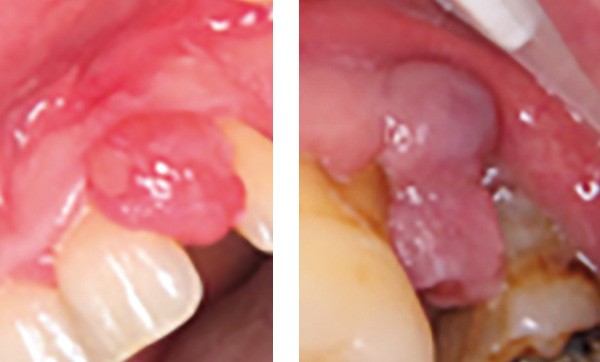

Examen clinique. Il révélait une lésion nodulaire de 1 cm de grand axe, localisée entre 21 et 22 en malposition. Le nodule était érythémateux et ulcéré sur sa face vestibulaire. Il présentait un caractère sessile. Le sondage à hauteur de la 21 mettait en évidence une poche parodontale de 5 mm au niveau distal.

Synthèse. Le tableau clinique et l’examen anatomopathologique sont évocateurs d’une épulis fibroblastique ulcérée calcifiante et ossifiante. Cette forme se distingue des épulis inflammatoires et fibreuses par la présence d’une ulcération et d’une métaplasie calcifiante et osseuse. Le traitement repose sur l’exérèse et un suivi, car cette forme clinique est plus récidivante que les épulis fibreuses ou inflammatoires simples.

Motif de la consultation. Patient de 49 ans venu consulter pour une tuméfaction en distal de 26.

Histoire de la maladie. La lésion était présente depuis 8 mois sans tendance spontanée vers la régression.